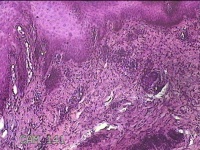

左侧足趾皮下结节

性别

女

年龄

32岁

临床诊断

皮下结节

一般病史

发现左侧足趾皮下结节2年余,无明显疼痛及不适。

标本名称

大体所见

灰白暗红色带皮肤肿物0.8x0.5x0.3cm一个,表面糜烂,切开结节呈实性,切面灰白暗红色,质中。